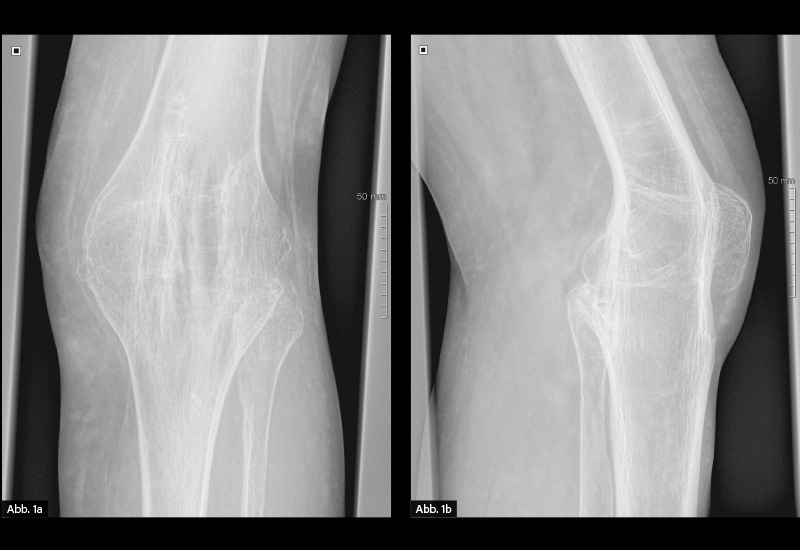

BILDGEBENDE DIAGNOSTIK: Röntgen (s. u.)

DIAGNOSE: Vollständige Ankylose des linken Kniegelenks